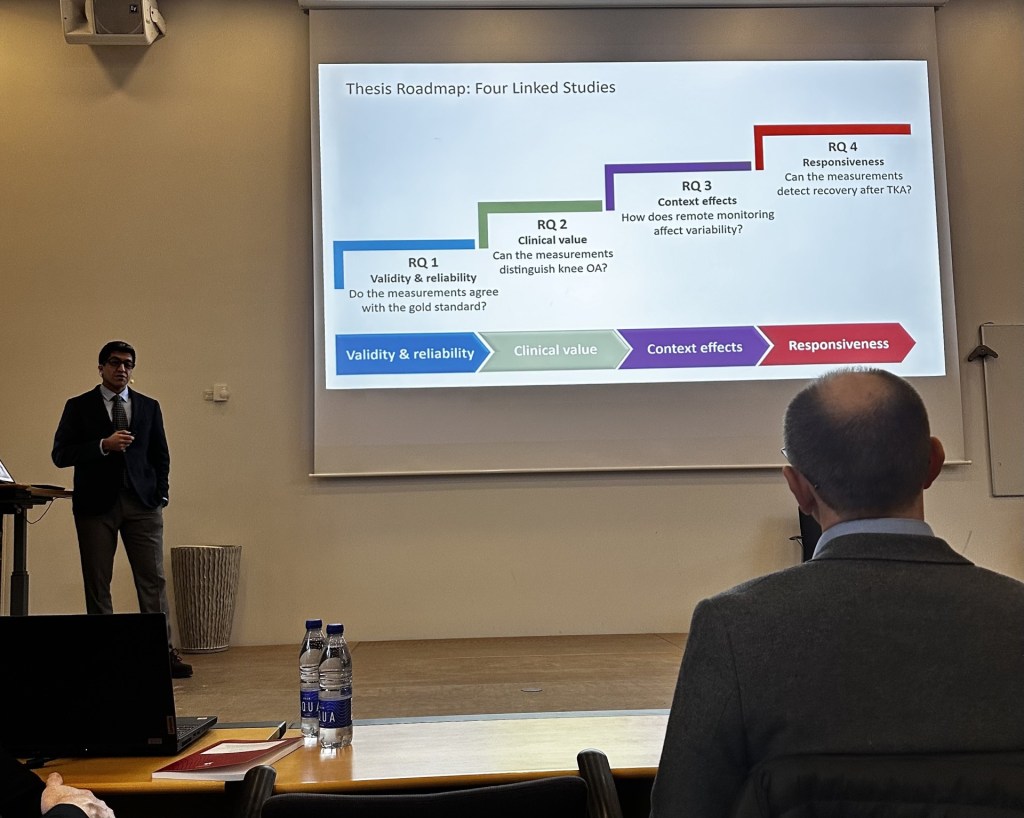

ABSTACT PRÆSENTERET VED ECR24

Til European Society of Radiology European congress of radiology 2024,… Læs mere